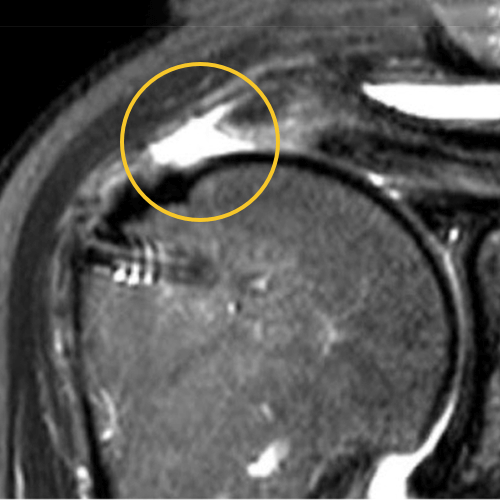

This is one of my cases, a 55-year-old woman, when her primary rotator cuff repair was done, we used Dermis on Demand, which is an allograft skin that can be utilized to help strengthen repairs. At four months out, the patient presented with pain and weakness following a traumatic injury and wound up re-tearing.

You can see a clear retear to the rotator cuff here with slight retraction, and some degeneration and thickness to the tendon.

This was not a softball case. Many aren’t. These are the complex rotator cuffs that worry you at night... Are you going to be able to fix it? Yes. But will it heal? That's the challenge. And that's where this implant helps you on a day-to-day basis.

We published this case study in the JOEI (Journal of Orthopedic Experience and Innovation) Journal. We did a revision of the large type-II repair and augmented it with BioBrace®. You can see the pre-op and three-month MRI below. Still fluid in the subacromial space but that tendon is clearly coming across into the footprint. Then, an eight-month MRI shows there's no further fluid in the subacromial space and maturation of that repair across the footprint.

Pre-OP

3 Months